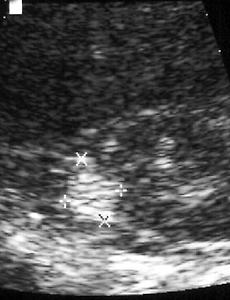

Angiomyolipoma.tuberous sclerosis Clinical History: None given. Findings: Ultrasound of the right kidney demonstrates a 1.5 cm round hyperechoic structure within the renal parenchyma. Computed tomography demonstrates a 1.5 cm heterogeneous, but primarily low density right renal lesion with intermixed regions of fat attenuation. Diagnosis: Angiomyolipoma. Discussion: An angiomyolipoma is a hamartoma consisting of fat, smooth musc.. 2009. 9. 8. 이전 1 다음